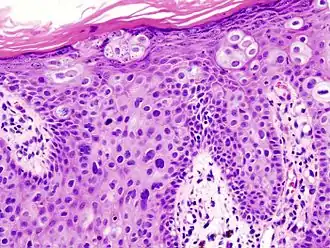

Histopathologically, the epidermis in cSCC in situ (Bowen's disease) will show hyperkeratosis and parakeratosis. There will also be marked acanthosis with elongation and thickening of the rete ridges. These changes will overly keratinocytic cells, which are often highly atypical and may have a more unusual appearance than invasive cSCC. The atypia spans the full thickness of the epidermis, with the keratinocytes demonstrating intense mitotic activity, pleomorphism, and greatly enlarged nuclei. They will also show a loss of maturity and polarity, giving the epidermis a disordered or "windblown" appearance.

Two types of multinucleated cells may be seen: the first will present as a multinucleated giant cell, and the second will appear as a dyskeratotic cell engulfed in the cytoplasm of a keratinocyte. Occasionally, cells of the upper epidermis will undergo vacuolization, demonstrating an abundant and strongly eosinophilic cytoplasm. There may be a mild to moderate lymphohistiocytic infiltrate detected in the upper dermis.[12]

Histopathology of squamous-cell carcinoma in situ (black arrow), compared to normal skin, showing marked atypia. -

Squamous-cell carcinoma in situ, showing prominent dyskeratosis and aberrant mitoses at all levels of the epidermis, along with marked parakeratosis.[12]